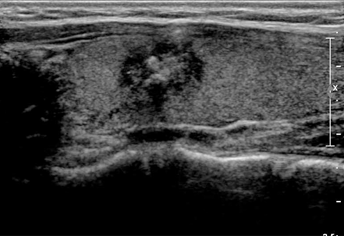

°©»ó¼±ÀÇ ¼¼Ä§ÈíÀÎ °Ë»ç·Î Á¶Á÷ÀÇ ¼º»óÀ» Á¤È®ÇÏ°Ô ÆÄ¾ÇÇϱ⠾î·Á¿î ¿©Æ÷¼º Á¾±«³ª, µüµüÇØ¼ ¼¼Æ÷ÀÇ ÈíÀÎÀÌ ¾î·Á¿î Á¾±«´Â Á¶Á÷°Ë»ç ¹æ¹ýÀ» ÀÌ¿ëÇÕ´Ï´Ù.

Ư¼ö ¹Ù´ÃÀ» »ðÀÔÇÏ¿© Á¶Á÷ÀýÆíÀ» äÃëÇϴµ¥ ȤÀÇ Å©±â¿¡ µû¶ó 2¹ø ~ 5¹ø±îÁöµµ ÇÒ ¼ö ÀÖ½À´Ï´Ù.

¼¼Ä§ÈíÀκ¸´Ù ´õ Á¤È®ÇÑ Áø´ÜÀ» ³»¸± ¼ö ÀÖÀ¸¸ç ¹Ù´ÃÀÌ µé¾î°¥ Á¤µµÀÇ »óó¸¸À» ³²±â±â¿¡ ÈäÅͰ¡ »ý±âÁö ¾ÊÀ¸¸ç Àý°³ÇÏ¿© Á¶Á÷ °Ë»çÇÏ´Â ¹æ¹ý°ú ºñ±³ÇÏ¿©µµ Á¤È®µµ°¡ ¶³¾îÁöÁö ¾Ê´Â °í³À̵µÀÇ Á¶Á÷°Ë»ç ¹æ¹ýÀÔ´Ï´Ù.

¾ãÀº º¼Ææ½É ±½±âÀÇ ¹Ù´Ã·Î »ý°¢º¸´Ù ¹Ù´ÃÀÌ ±½±â ¶§¹®¿¡ ±¹¼Ò¸¶Ã븦 ¸ÕÀú ÇÑ µÚ¿¡ °Ë»ç¸¦ ½ÃÇàÇØ¾ß Çϸç, »ç¿ëÇÏ´Â ±â±¸°¡ ÀÏȸ¿ëÀ̱⿡ ºñ¿ëÀÌ ´õ µç´Ù´Â °Í°ú ÃâÇ÷ÀÌ Á» ´õ ¸¹°í, °Ë»ç ÈÄ ÅëÁõÀÌ ¿À·¡°£´Ù´Â ´ÜÁ¡ÀÌ ÀÖ½À´Ï´Ù.